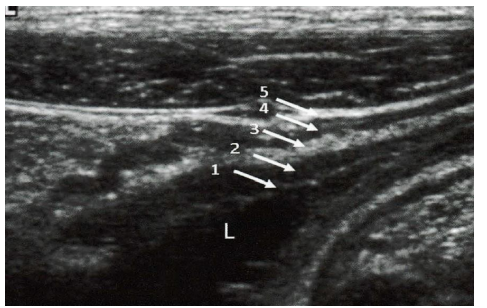

Qual a relação

CORRETA

em relação as camadas intestinais numeradas a partir do lúmen da alça:

1-Interface entre o conteúdo luminal e a mucosa 2-muscular própria 3-submucosa 4-muscular da mucosa 5-interface entre a serosa e a muscular.

1-Interface entre o conteúdo luminal e a mucosa 2-muscular da mucosa 3-submucosa 4-muscular própria 5-interface entre a serosa e a muscular.

1-Interface entre o conteúdo luminal e a serosa 2-muscular da mucosa 3-submucosa 4-muscular própria 5-interface entre a serosa e a muscular.

1-Interface entre o conteúdo luminal e a serosa 2-muscular própria 3-submucosa 4-muscular da mucosa 5-interface entre a serosa e a muscular.